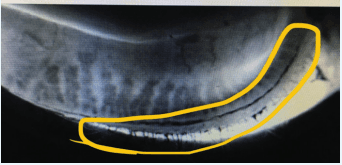

In Figure 2, meibography of the meibomian gland orifices show eyeliner residue. Tightlining an eyeliner increases the risk of meibomian gland dysfunction and gland obstruction.

https://covalentcareers3.s3.amazonaws.com/media/original_images/Eyeliner_residue.png

Figure 2